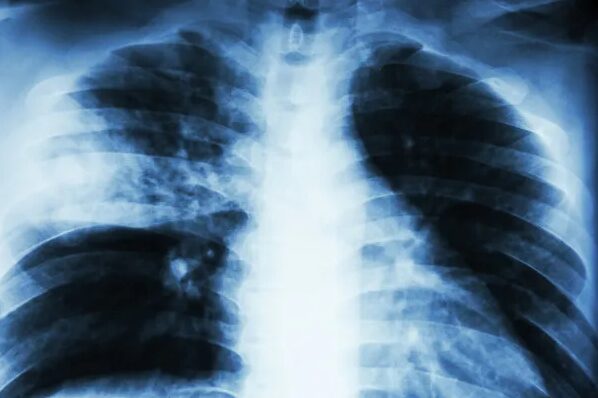

A pneumonia silenciosa, também conhecida como pneumonia assintomática ou subclínica, pode ser particularmente perigosa porque não apresenta os sintomas típicos da pneumonia, como febre alta, tosse intensa e dor no peito.

Segundo a infectologista, a pneumonia silenciosa geralmente apresenta sintomas menos intensos e pode durar mais tempo. O paciente pode ter uma tosse persistente que não melhora com antibióticos e a condição pode não ser identificada imediatamente.

Outros sintomas observados incluem febre, falta de ar, indisposição e falta de apetite. Em crianças, é importante observar a diminuição da diurese (menos urina) e sinais de prostração, sonolência ou confusão. Em idosos, os sintomas podem ser menos evidentes e mais difíceis de identificar.

É importante destacar que a enfermidade pode afetar qualquer pessoa. Os principais grupos de risco são idosos, crianças, pessoas com doenças pulmonares pré-existentes, e aqueles com imunossupressão, como pacientes com HIV, em tratamento de quimioterapia ou em uso de medicamentos imunossupressores.

O diagnóstico da pneumonia silenciosa pode ser feito de forma simples com o painel molecular, que examina o muco ou o catarro do paciente. Também é possível usar exames de cultura para identificar as bactérias envolvidas.

“Os exames de painel molecular, que procuram o DNA da bactéria, são geralmente rápidos. As culturas podem levar mais tempo, mas o painel molecular é bem ágil,” explica Roriz.

O tratamento de suporte, como oxigênio e cuidados gerais, é semelhante em diferentes formas de pneumonia. No entanto, o tipo de antibiótico pode variar.

“O tratamento pode exigir antibióticos específicos para essas bactérias atípicas”, pontua a médica.